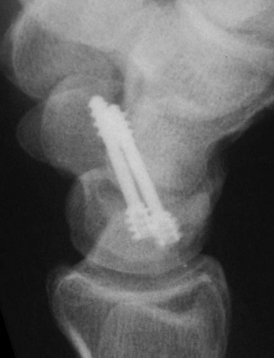

Case 7. This nonunion patient's scaphoid and iliac crest were unusually soft bone.

Click for larger image

After two screws, the fixation was clearly inadequate, so I put a third screw through the graft into the proximal pole. I wasn't sure whether to buy

stock in Herbert screws or Zantac. The fracture healed despite AWOL and no immobilization.